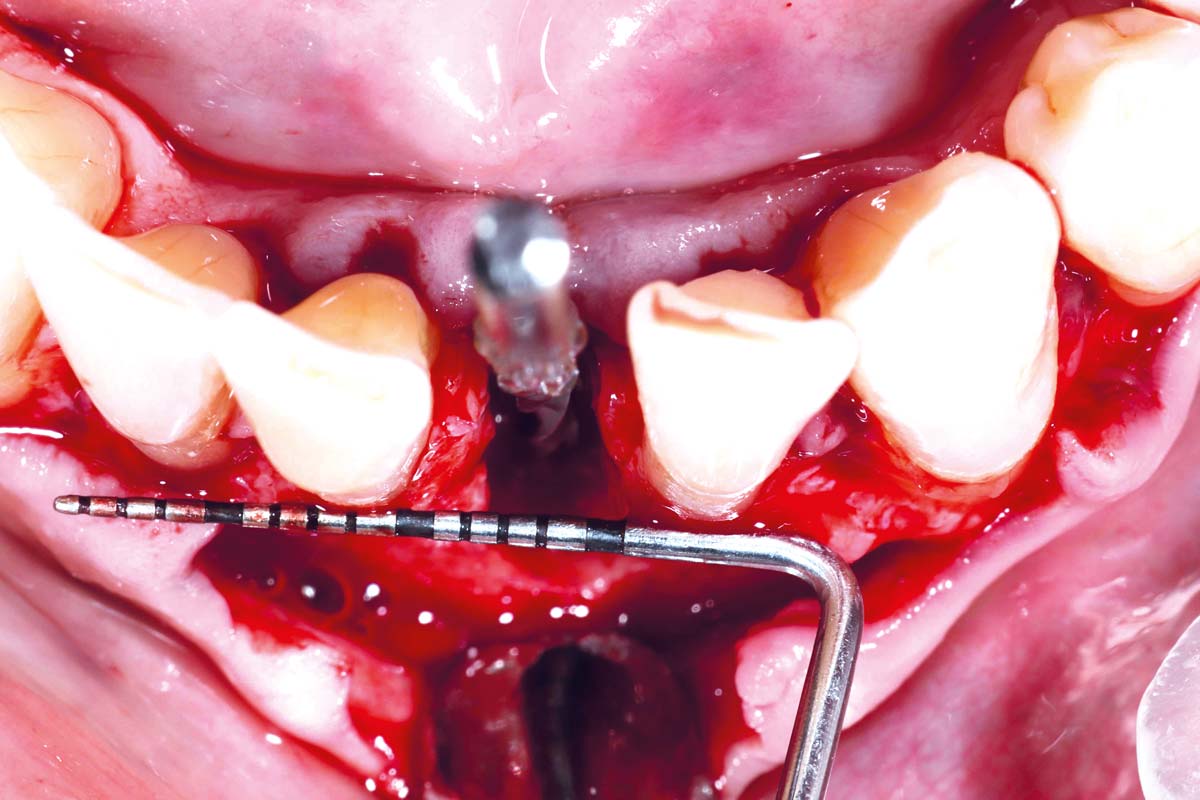

Immediate implant placement using cerabone® and collagen fleece - Dr. D. Jelušić